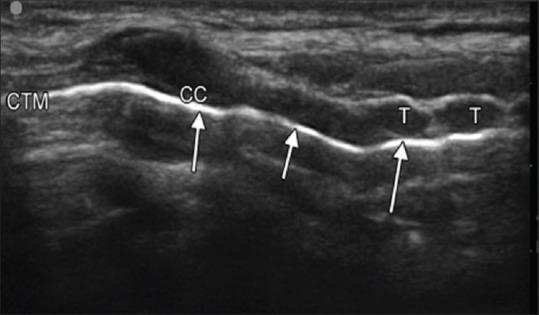

After the detection of novel coronavirus (2019) as the cause of a cluster of pneumonia in Wuhan, China, at the end of 2019, more than 10 million confirmed cases of coronavirus disease 2019 (COVID-19) have been reported around the globe. In the COVID-19 intensive care unit (ICU), the use of stethoscope is minimal for obvious reasons. Shifting of COVID-19 patients out of ICU setup increases the risk of transmission of infection to health-care workers as well as jeopardizes the safety of patients. Hence, diagnostic imaging has emerged as a fundamental component of the current management of COVID-19. Lung ultrasound (LUS) imaging has become a safe bedside imaging alternative that does not expose the patient to radiation and minimizes the risk of contamination. Ultrasound (USG) can be used to scan almost all vital organs (heart, kidney, vascular, brain, etc.) and also help in rapid decision-making regarding the management of COVID-19 patients. In this note, we review the current state of the art of LUS in evaluating pulmonary changes induced by COVID-19. The goal is to identify characteristic sonographic findings most suited for the diagnosis of COVID-19 pneumonia infections as well as to assess the impact of infection on other organs and utilizing the same in the management of COVID patients without compromising on the safety of patient or health-care provider.

2019年末在中国武汉发现新型冠状病毒(2019)是一组肺炎病例的病因后,全球已报告超过1000万例2019冠状病毒病(COVID-19)确诊病例。在COVID-19重症监护病房(ICU),由于显而易见的原因,听诊器的使用极少。将COVID-19患者转出ICU会增加感染传播给医护人员的风险,同时也危及患者安全。因此,诊断成像已成为当前COVID-19管理的一个基本组成部分。肺部超声(LUS)成像已成为一种安全的床旁成像选择,不会使患者暴露于辐射下,并将污染风险降至最低。超声(USG)可用于扫描几乎所有重要器官(心脏、肾脏、血管、大脑等),也有助于对COVID-19患者的管理做出快速决策。在本笔记中,我们回顾了LUS在评估COVID-19引起的肺部变化方面的当前技术水平。目标是确定最适合诊断COVID-19肺炎感染的特征性超声表现,以及评估感染对其他器官的影响,并在不损害患者或医护人员安全的情况下将其用于COVID患者的管理。